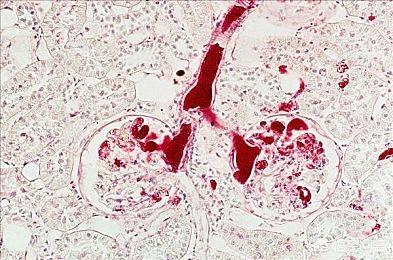

まず第一に、漢方医学における脾臓は、現代医学における脾臓とは異なり、免疫調節や老化した血球の貪食を行う末梢免疫器官である。漢方における脾臓は、消化器官全体の生理機能をカバーするもので、基本的には「脾は食水穀を運ぶ主人」という言葉に体現されている。 また、脾臓の機能には、気血の生成、津液の清散促進、臓腑がたるまないように持ち上げる、血液が静脈外に溢れないように統一するなどの生理的役割がある。人体が誕生して以来、飲食物を運び、気血を生成して全身を滋養するのは脾臓に頼っているので、食生活の乱れ、過度の空腹感や満腹感、情緒障害などは脾臓の気を損傷する可能性が高く、脾臓の気が弱った後に機能が低下するのが脾気虚であり、朱医師は臨床診断を通して、脾気虚の人の多くは軽度の胃部不快感、食欲不振、緩い便通などの胃腸機能を低下させる機能性病態を示すだけであることを発見した。機能性ディスペプシア、慢性表層性胃炎、胃下垂など。脾虚が長期化すると、器質的な病変を引き起こし、他の内臓にまで影響を及ぼし、多くの病気や実質的な損傷を引き起こす可能性がある。例えば、水腫、動悸、不眠症、黄疸、小児栄養失調、慢性萎縮性胃炎などである。では、脾虚の原因は何でしょうか?具体的な疾患分類は?

- 脾虚は脾臓が病原因子によって刺激されることで起こり、最初は主に機能障害である。例えば、たまに食事を食べ過ぎて消化不良を起こすのは脾気が損なわれている問題だが、通常は大きな影響はない。もし脾気が持続的な食生活の乱れや感情の乱れによって損なわれると、次のような形で現れる。脾気虚、気虚は機能低下が支配的である。 病気が進行すると、気虚は脾陽虚に発展し、この時、陽気の温め促進する力が弱まり、これを基盤として水滞を伴う陽虚、瘀血を伴う陽虚など多くの病的変化が起こる。初期の脾気虚は通常、重篤な疾患を伴わず、消化不良などの脾胃の症状のみである。後期になると、脾陽虚、脾虚、水飲湿滞が現れる。瘀血と気滞を伴う脾虚はより複雑で、慢性消化器疾患、萎縮性胃炎、黄疸、水腫などの実質的な病変を伴うことが多い。脾虚の一般的な証拠は以下の通りである:

- (iii) 脾陽虚:多くは脾気虚のさらなる悪化によるもので、脾陽の温める能力の低下として現れ、脾気虚の随伴症状に加えて、多くは四肢の温感、唾液過多、明らかな胃の冷えへの恐怖、嘔吐、下痢を伴い、寒さによって悪化し、熱によって緩和する。陽虚、寒証、瘀血、腹部膨満感、鼓のように膨らむ、腹腔内に液体が貯留する、臍が盛り上がる、腱が露出する、陽虚、水飲停滞、湿滞、肝胆閉塞、黄疸。舌は蒼白で水苔と点状出血があり、脈は鈍く細い。これは脾虚の重症例で、機能性疾患でも起こりうるが、肝硬変、重症胃炎、慢性膵炎などの器質性疾患に多くみられる。